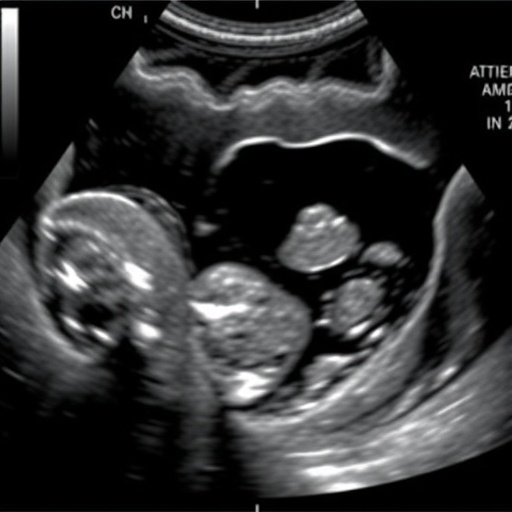

The researchers, led by de Souza Pires and colleagues, utilized ultrasound as a non-invasive imaging technique to assess infants post-omphalocele repair. This approach is particularly valuable in pediatrics, where minimizing invasive procedures is a priority. The study’s findings highlight how ultrasound can effectively visualize changes in the abdominal cavity that signify the onset of compartment syndrome.

In their research, the team established specific ultrasound criteria for identifying ACS, which could serve as a guideline for practitioners in the neonatal intensive care units. This is particularly crucial as neonates are often unable to verbalize their discomfort or distress, making traditional diagnostic methods less effective. The ability to rely on ultrasound can help clinicians make informed decisions about the management of these vulnerable patients.

Article Title: Ultrasound findings of abdominal compartment syndrome after omphalocele repair.

de Souza Pires, P., Cortada Lluelles, R. & Arenos, J. Ultrasound findings of abdominal compartment syndrome after omphalocele repair.